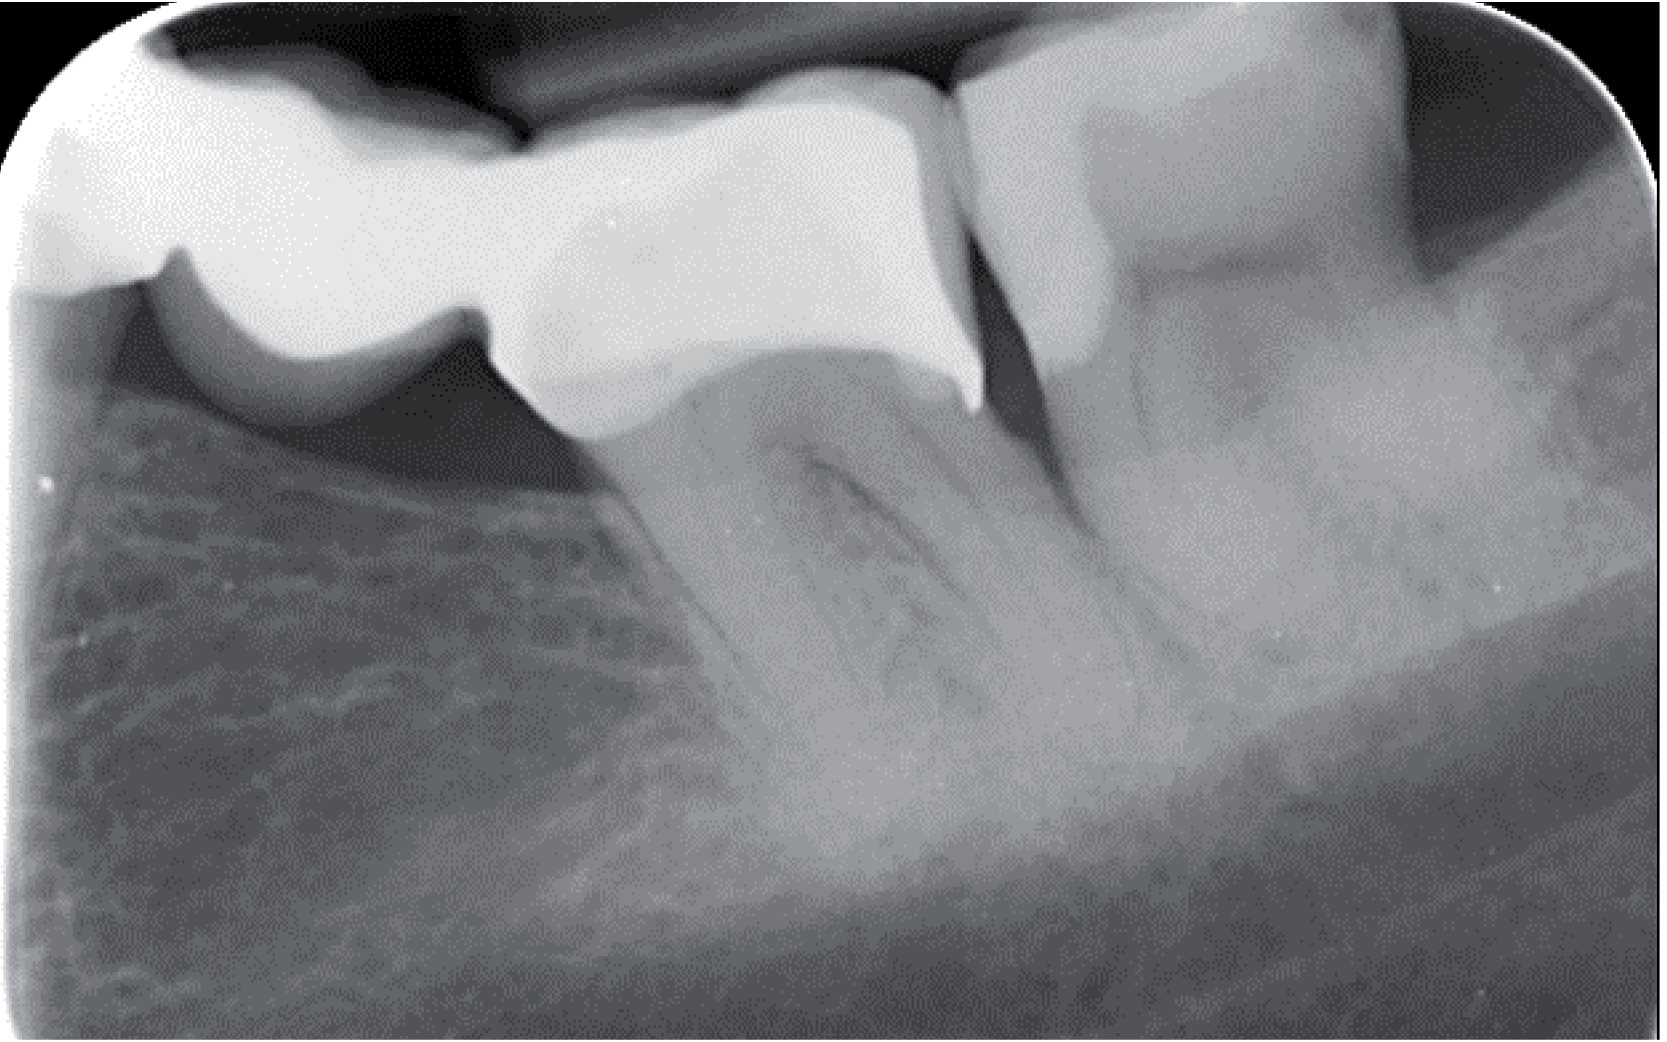

Fig. 3 Etter applisering av EQUIA Forte

Etter matrisen og kilen er satt, gir sug og bomullsrull en tilstrekkelig fuktighetskontroll. Dentin Conditioner fra GC ble brukt, i henhold til bruksanvisningen, før tannen ble fylt med ett lag Equia Forte, i em bulk. Deretter presses det med en mikrobørste på fyllingen for å oppnå en god binding til dentinet. (Fig.3) Etter 2½ min. av initiell herdetid, fjernes matrisen forsiktig. Overflødig fyllingsmateriale poleres vekk og resten av fyllingen finpoleres med en rød pussediamant og Sof-Lex-skiver.